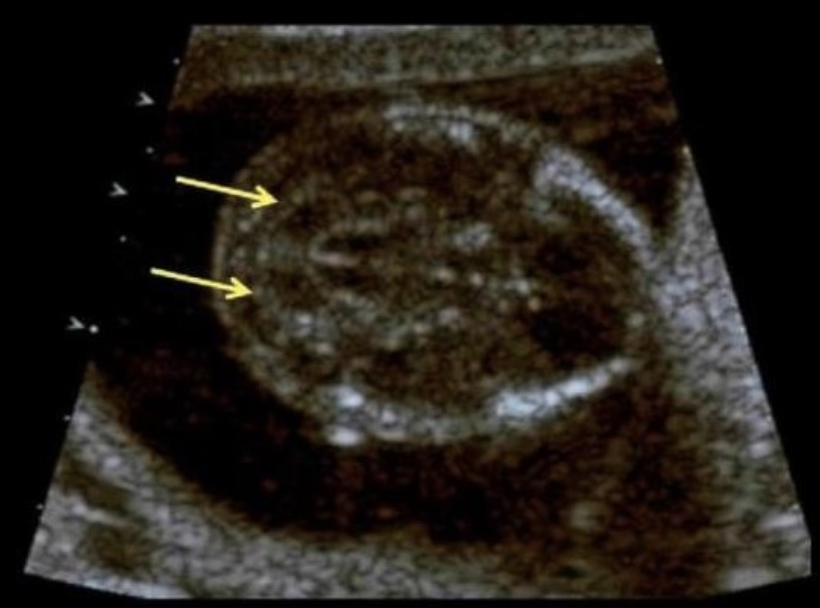

what type of CCAM is this

a) 1

b) 2

c) 3

d) 4